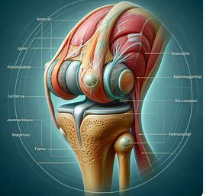

슬개골연골연화증은 무릎 앞쪽에 위치한 슬개골의 연골이 약해지거나 손상되어 발생하는 질환입니다. 슬개골연골연화증은 무릎 관절에서 중요한 역할을 하는 연골이 부드러워지거나 파열되는 상태로, 주로 젊은 성인과 운동선수들에게서 빈번히 나타납니다. 슬개골연골연화증은 과도한 사용, 외상, 유전적 요인, 불균형한 근육 발달 등이 원인이 될 수 있습니다.